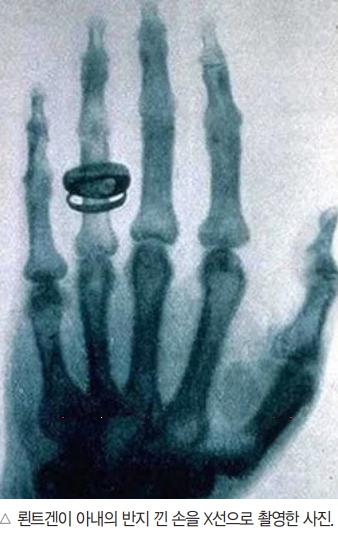

이 가설을 검증하기 위해 뢴트겐은 아내를 설득해 음극선관과 건판 사이에 손을 놓아보라고 했다. 스위치를 누르고 건판을 현상해 보니 뼈의 윤곽은 뚜렷하게, 뼈 부근의 근육은 희미하게 그려져 있었다. 역사상 처음으로 살아있는 사람의 뼈가 사진으로 찍힌 순간이었다. 수학에서 모르는 양을 흔히 X로 표시하듯 뢴트겐은 이 빛을 X-선이라고 이름 붙였다.

그 해 12월 28일, 뢴트겐은 ‘새로운 종류의 광선에 대하여’라는 제목으로 뷔르츠부르크 물리학·의학협회에 논문을 제출했다. 50세가 넘은 1895년 초까지 크게 주목받지 못한 48편의 학술논문을 발표했던 뢴트겐이 일약 세계적으로 유명한 과학자가 되는 순간이었다. 논문 발표 1년 만에 X-선에 관한 논문이 1000편, 단행본이 50권 가량 출판됐다. 1897년에는 뢴트겐협회가 결성됐고, 뢴트겐은 1901년에 제1회 노벨 물리학상을 수상했다.